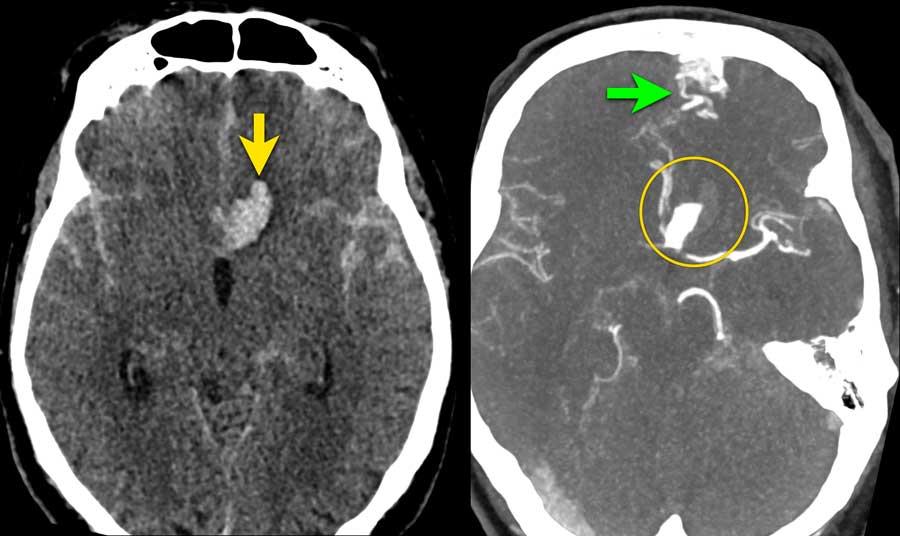

Bệnh nhân này nhập viện với triệu chứng đau đầu dữ dội khởi phát cấp tính.

Máu được phát hiện tại ba vị trí khác nhau:

- Trong não thất bên và não thất IV (mũi tên vàng)

- Trong nhu mô não tại vùng nhộng tiểu não (mũi tên xanh lá)

- Dưới nhện tại bể trước cầu não và lỗ chẩm (dấu hoa thị)

Tiếp tục với CTA…

CTA cho thấy động mạch tiểu não sau dưới (PICA) nổi bật (mũi tên vàng) với một túi phình hình túi 7 mm (vòng tròn) nằm tiếp giáp với nhộng tiểu não.

Có một tĩnh mạch giãn (mũi tên xanh dương) dẫn lưu trực tiếp vào xoang thẳng.

Giữa động mạch bất thường (PICA kèm túi phình) và tĩnh mạch bất thường, quan sát thấy một mạng lưới các cấu trúc mạch máu nhỏ (đầu mũi tên), nghi ngờ là nidus.

Tiếp tục với DSA…

DSA xác nhận PICA phải kèm túi phình (mũi tên) dẫn đến nidus (vòng tròn).

Nidus được dẫn lưu bởi cả tĩnh mạch nông và tĩnh mạch sâu (không hiển thị riêng biệt ở đây).

Các phát hiện phù hợp với AVM – Spetzler-Martin độ 2:

- Nidus nhỏ (<3 cm): 1 điểm

- Vị trí vùng não không chức năng quan trọng: 0 điểm

- Kiểu dẫn lưu tĩnh mạch bao gồm cả thành phần nông và sâu: 1 điểm

Túi phình hình túi xuất phát từ PICA được giải thích là túi phình liên quan đến dòng chảy.

Do sự thay đổi huyết động học gây ra bởi AVM, thành mạch có thể bị suy yếu và hình thành túi phình.

Các hình ảnh cho thấy DSA trước và sau khi đặt coil túi phình.

PICA, nidus và các tĩnh mạch dẫn lưu bất thường (cùng tạo thành AVM) vẫn còn ngấm thuốc tương phản.

Quyết định không điều trị trực tiếp AVM mà lựa chọn theo dõi và có thể can thiệp phẫu thuật trong tương lai.